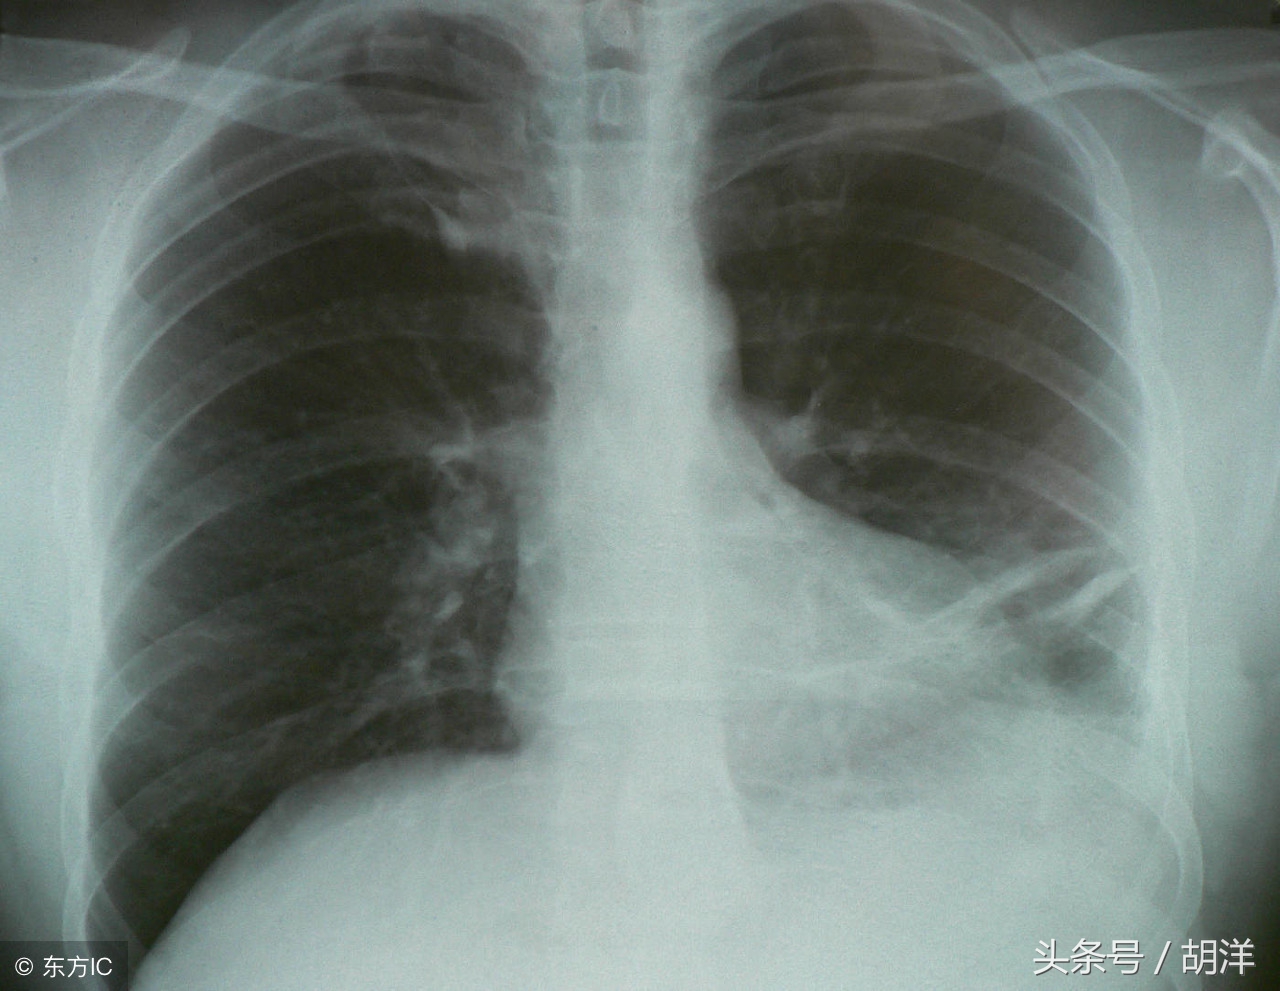

肺粘液表皮样癌的肿瘤组织里里既有粘液细胞也有表皮样细胞,主要起源于支气管树的小黏液腺,这种肺癌好发于气管和支气管,一般生长缓慢,早期无明显症状,当肿瘤逐渐增大后容易刺激和阻塞气道,引起咳嗽、气喘等症状,其症状与其他肺癌相似,没有特异性。